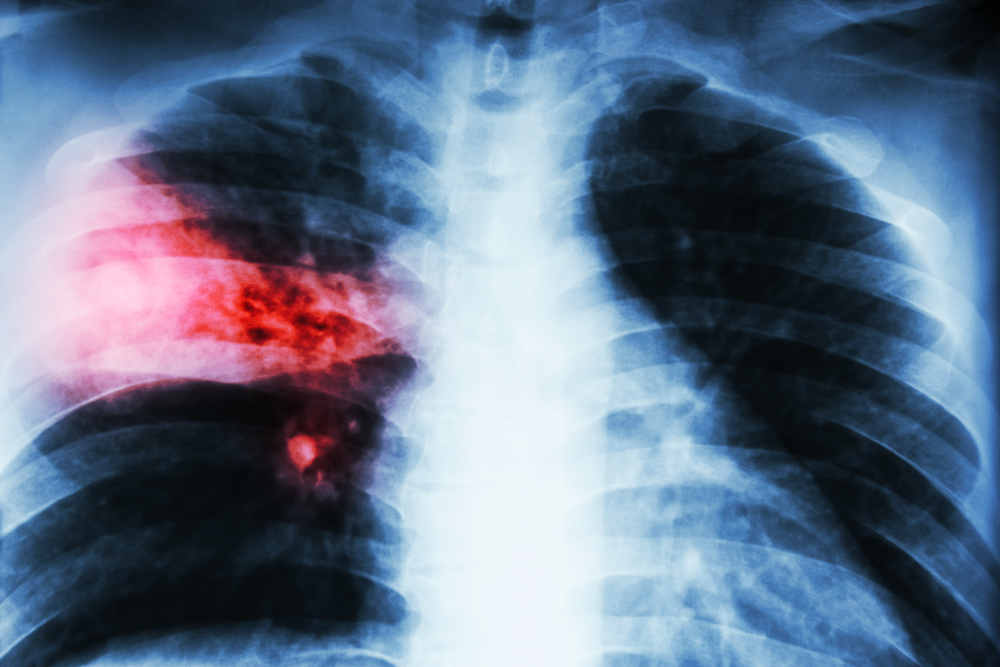

ফুসফুস ক্যানসারের অন্যতম লক্ষন হচ্ছে দীর্ঘমেয়াদী কাশি হওয়া, কখনো কখনো কাশির সঙ্গে কফ এবং কফের সঙ্গে রক্ত যাওয়া। ফুসফুসের ক্যানসারের কারণে বুকে ব্যথা হতে পারে। ক্যানসার যদি ব্যাপকতা পায় এবং বুকে পানি চলে আসে অথবা ফুসফুসে বেশি ছড়িয়ে পড়লে শ্বাসকষ্ট হতে পারে। এছাড়া কিছু সাধারণ লক্ষণ আছে, যেগুলো সব ক্যানসারেই দেখা যায়। যেমন- ওজন কমে যাওয়া, খাবারে অরুচি।